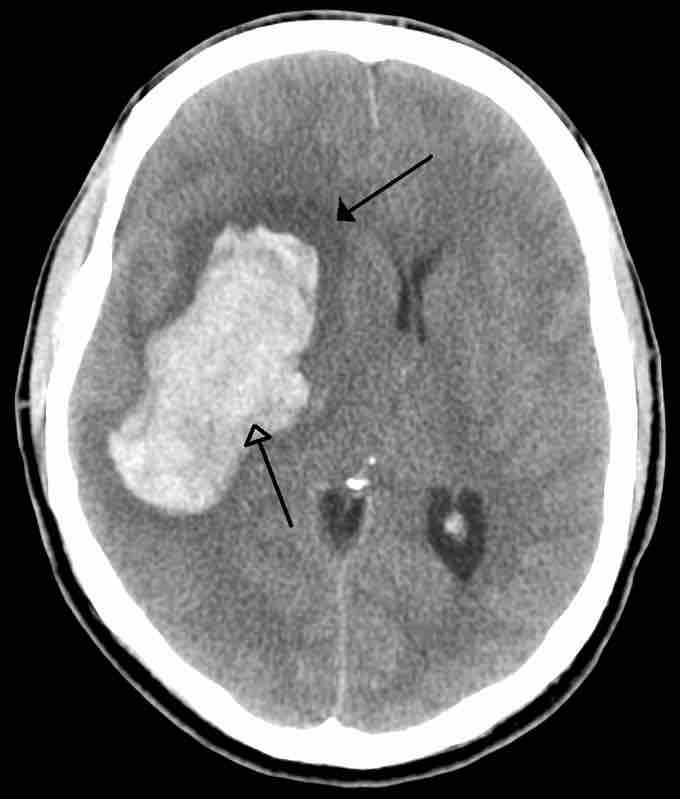

An Example of a Stroke

A intra-parenchymal bleed with surrounding edema.